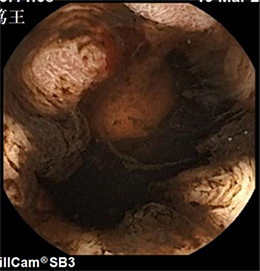

下图可见胃腔内新鲜出血与

陈旧性出血混合